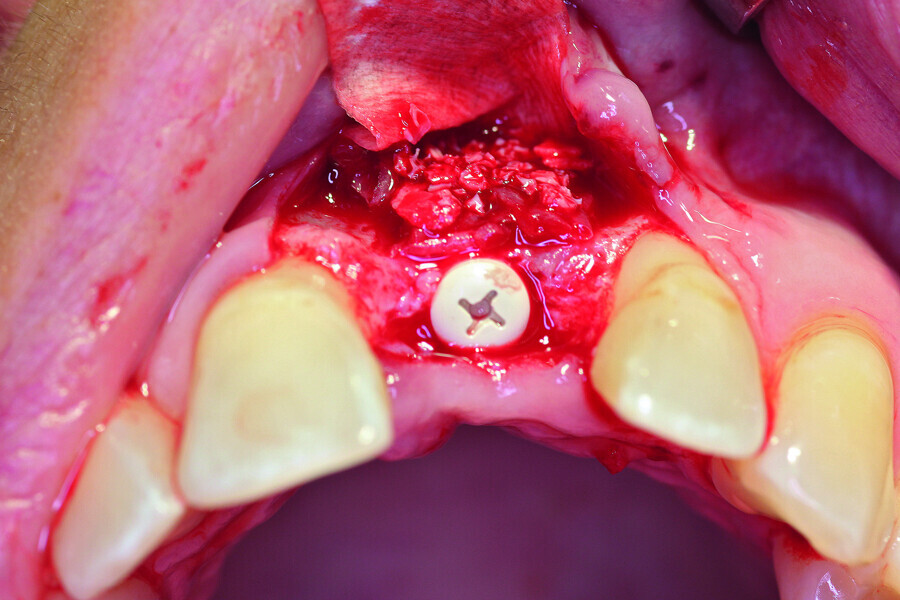

Fig. 6a: Transversal bone augmentation was performed.

Fig. 6b: Transversal bone augmentation was performed.